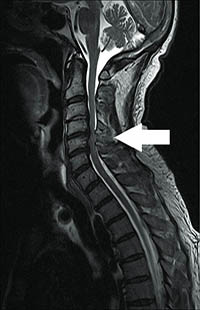

Dysfunction of spinal cord arising out of compression is called as compressive myelopathy. Most commonly the compression is seen due to degenerative changes in cervical spine (neck) called as cervical myelopathy or in the thoracic spine (mid back) called as thoracic myelopathy.

In cervical myelopathy both upper and lower limb is affected. In thoracic myelopathy only lower limb is affected.

Patient might present with clumpsiness of hands, difficulty in doing fine jobs with hands such as buttoning the shirt, change of handwriting and mixing the food. Change in gait pattern with unsteadiness and rigidity in limbs are other symptoms.

MRI is the best investigational modality for compressive myelopathy.

Treatment is mainly surgical decompression as early as possible. The disease will progress on delaying the surgery . The treatment is mainly to halt further progression.